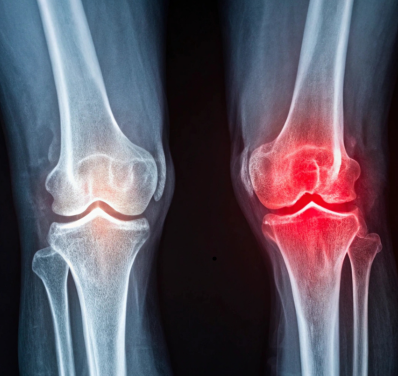

Osteoarthritis, often seen in older adults, is the most common form of arthritis. It occurs when the cartilage that cushions the joints breaks down over time, causing pain and stiffness, particularly in weight-bearing joints like the knees, hips, and spine.

As we age, joint tissue begins to wear down naturally. The breakdown of cartilage, along with the reduction of synovial fluid, makes joints less flexible, which often leads to pain, especially in the knees and hips.